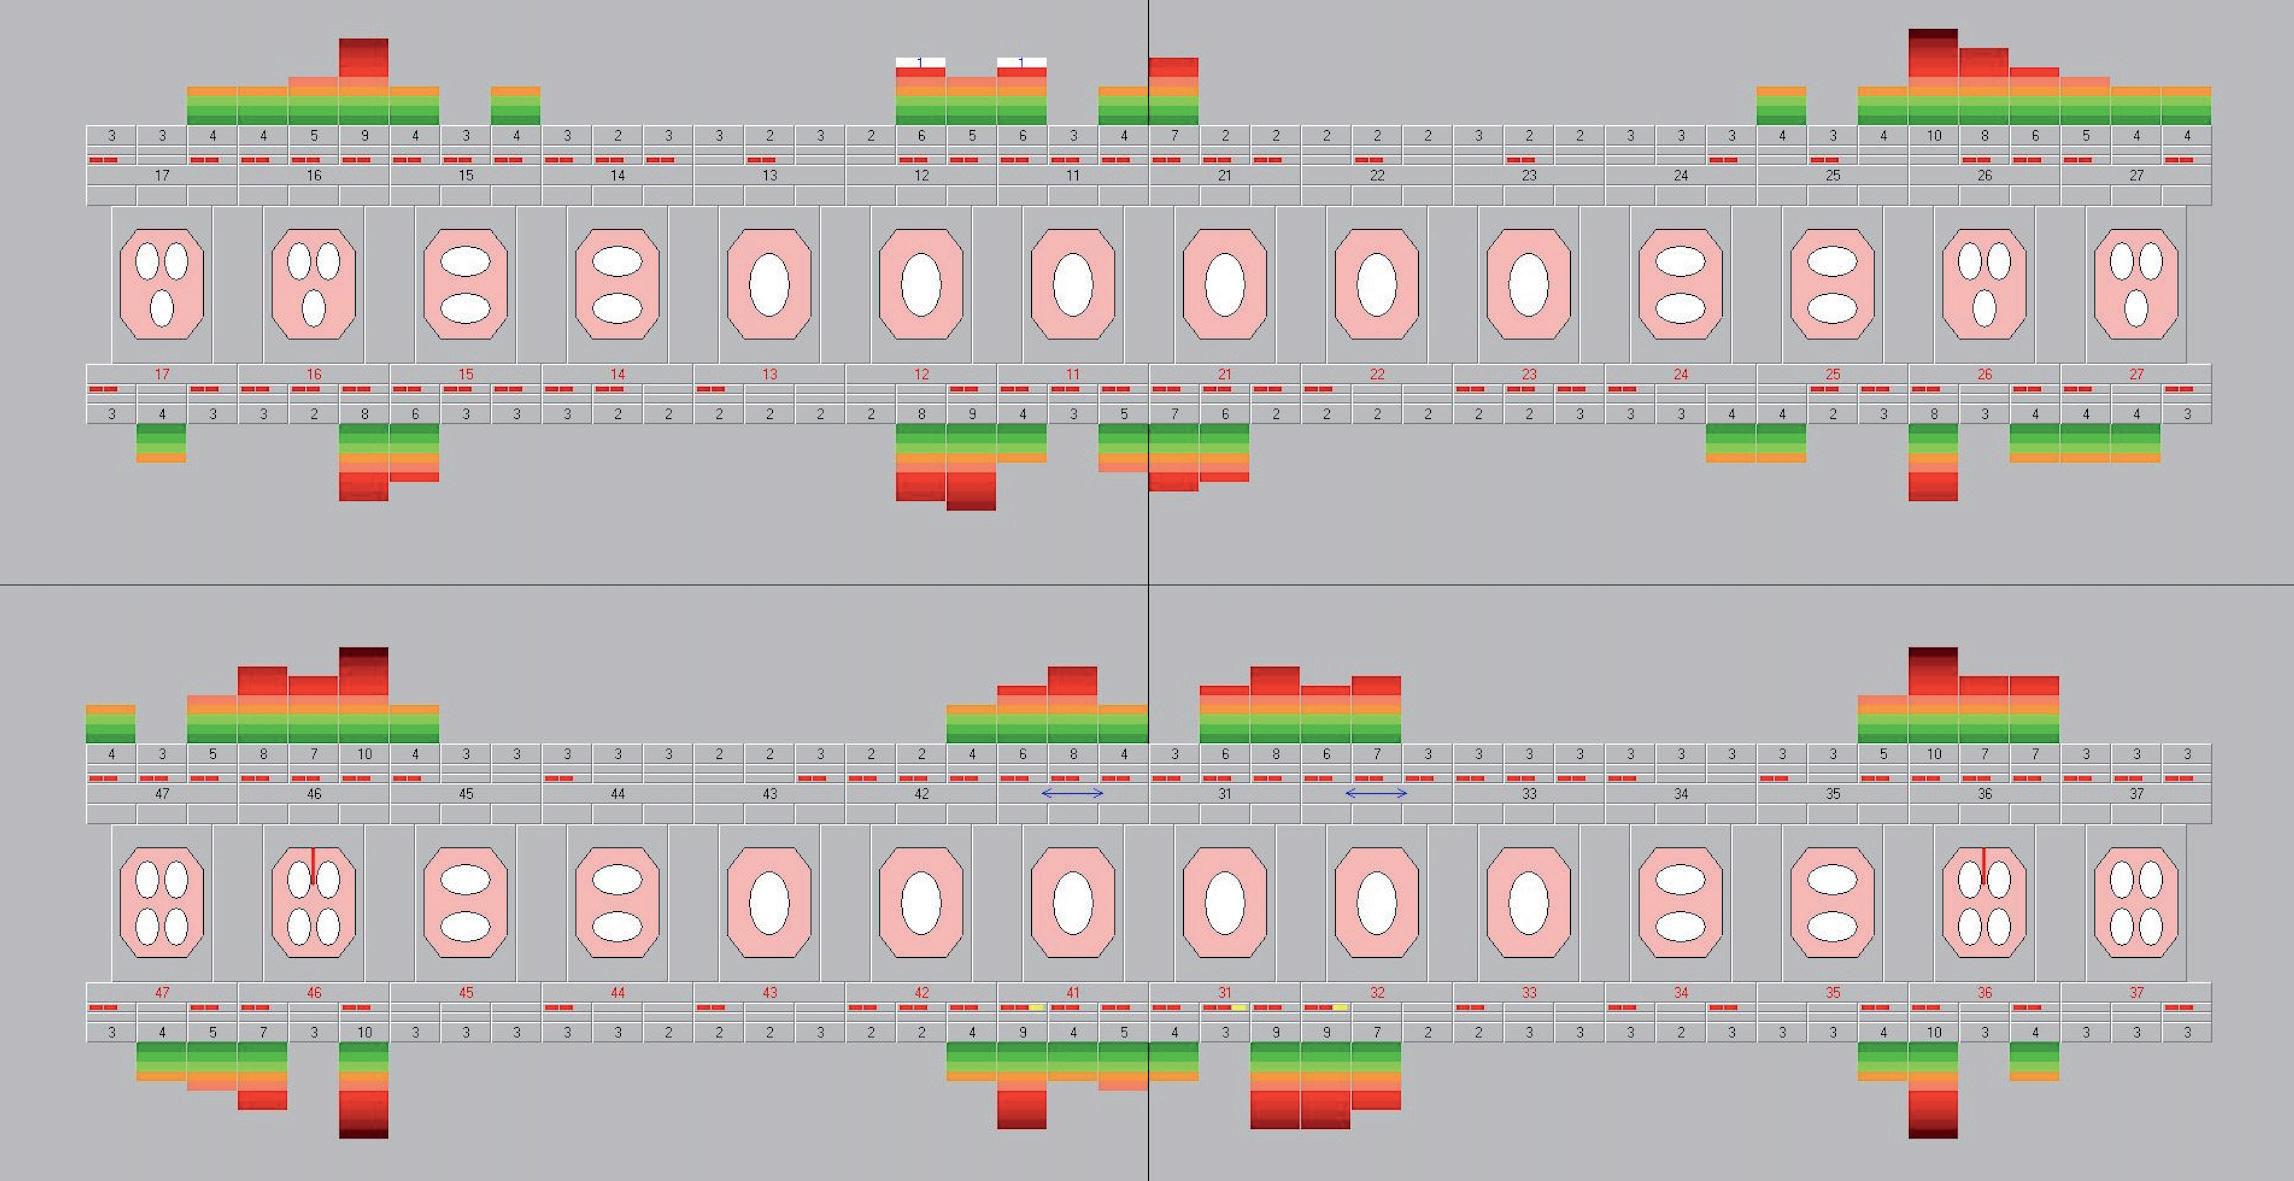

Klinisch was er inderdaad sprake van ernstige problematiek met bij de eerste molaren en de boven- en onderincisieven pockets tot 10 mm en diepe angulaire bot defecten met 50% botafbraak. Gegeneraliseerd is de gingiva ernstig ontstoken met een bloedingsscore van 67% (Afbeelding 3 en 4). Kortom, zeker gezien haar jon ge leeftijd, gegeneraliseerde parodontitis, vergevorderd snel progressief. Het gevolg daarvan was dat we haar direct moesten teleurstellen en aangeven dat een ortho dontische behandeling, zolang er sprake was van een parodontale ontsteking, er voorlopig niet in zat. Eerste prioriteit was nu het bereiken van een parodontaal zo op timaal mogelijke, gezonde situatie.

Afbeelding 3. Parodontiumstatus Intake (30-11-16)